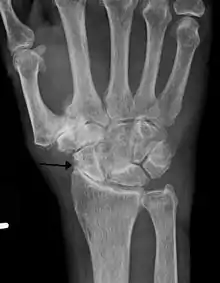

Diagnosis is made with reasonable certainty based on history and clinical examination.[42][43] X-rays may confirm the diagnosis. The typical changes seen on X-ray include: joint space narrowing, subchondral sclerosis (increased bone formation around the joint), subchondral cyst formation, and osteophytes.[44] Plain films may not correlate with the findings on physical examination or with the degree of pain.[45] Usually other imaging techniques are not necessary to clinically diagnose osteoarthritis.

- Severe osteoarthritis and osteopenia of the carpal joint and 1st carpometacarpal joint.